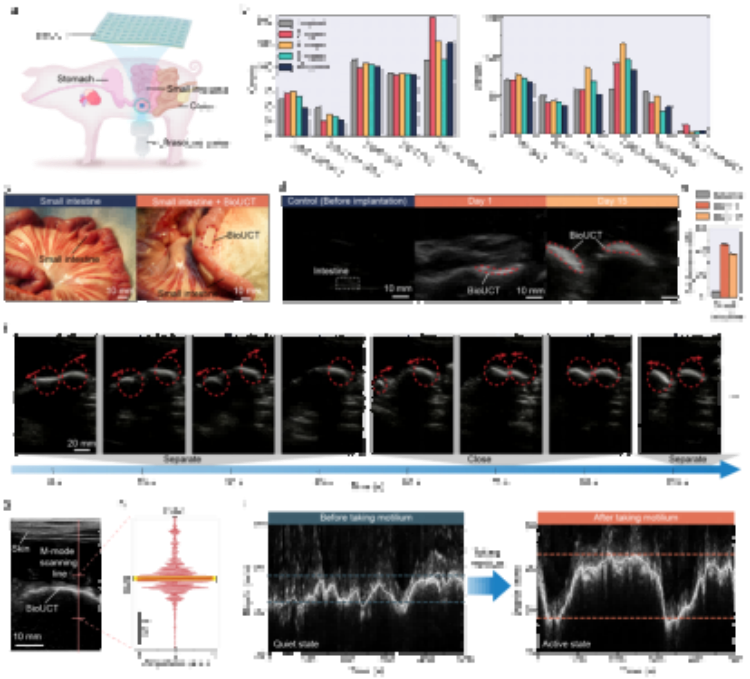

①革命性成像性能:從“看不見(jiàn)”到“高清追蹤”超強(qiáng)聲學(xué)反射(圖2a-b)通過(guò)周期性微氣囊設(shè)計(jì),BioUCT在體外測(cè)試的2MHz超聲下實(shí)現(xiàn)57dB頻譜信號(hào)增幅(較普通水凝膠),在實(shí)際動(dòng)物實(shí)驗(yàn)中將B超圖像亮度提升30dB,使腸道輪廓清晰顯現(xiàn)(圖2b)。時(shí)/頻域分析顯示其回聲強(qiáng)度遠(yuǎn)超軟組織(圖2a),解決了腸道超聲的信噪比受腸道“弱反射”限制的核心痛點(diǎn)。

抗形變穩(wěn)定性(圖2f-g)在50%拉伸及90°彎曲狀態(tài)下(模擬腸道蠕動(dòng)),B超/M超成像亮度波動(dòng)<5%(圖2f),相位監(jiān)測(cè)波形穩(wěn)定(圖2g),確保動(dòng)態(tài)監(jiān)測(cè)可靠性。

大角度成像能力(圖2c-e)探頭在深度(5-25cm)、角度(±30°)、水平位移(±20mm)變化時(shí),圖像亮度標(biāo)準(zhǔn)差<1.5dB(*n*=3),適配臨床操作誤差。

在對(duì)豬腸道蠕動(dòng)幅度監(jiān)測(cè)的驗(yàn)證實(shí)驗(yàn)中,操作人員通過(guò)臨床通用的超聲成像設(shè)備成功追蹤到服藥前后腸蠕動(dòng)幅度的變化(3.13mm→7.59mm)。該技術(shù)未來(lái)可結(jié)合可穿戴超聲設(shè)備,實(shí)現(xiàn)患者居家監(jiān)測(cè),特別適用于:小腸切除術(shù)后并發(fā)癥預(yù)警慢性腸梗阻患者長(zhǎng)期管理胃腸動(dòng)力藥效評(píng)估。

圖5. 通過(guò)BioUCT進(jìn)行活體動(dòng)物腸道運(yùn)動(dòng)監(jiān)測(cè)。